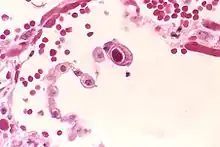

| Typical "owl eye" intranuclear inclusion indicating CMV infection of a lung pneumocyte[1] | |